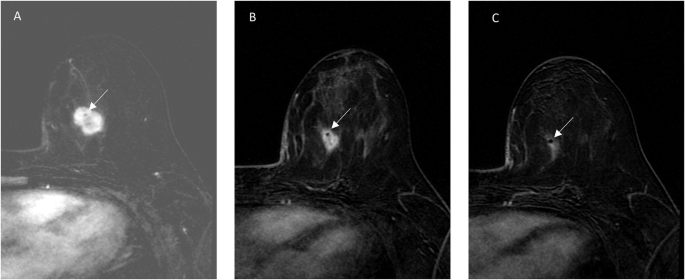

The clinical and tumor characteristics of the 287 patients included in the analysis are summarized in Table 1. Following NAST, 132 patients (132 of 287, 46%) achieved pCR, 64 (44.1%) in the discovery cohort and 68 (47.9%) in the validation cohort (Supplementary Data 1). NAST consisted of doxorubicin/cyclophosphamide (AC) for four cycles every 2 weeks followed by paclitaxel weekly for 12 doses. DCE-MRI after two and four cycles of AC was used for imaging response assessment (Fig. 1). Figure 2 shows a representative example of a patient with excellent treatment response following two and four cycles of NAST, with pCR confirmed by surgical pathology.

MRI at baseline (A), after two cycles (B), and four cycles (C) of AC shows an oval, heterogeneously enhancing mass with associated clip marker (arrows). MRI shows concentric shrinkage and tumor volume reduction of 83% after two cycles, and 96% after four cycles. Pathology after the completion of NAST confirmed pathologic complete response.